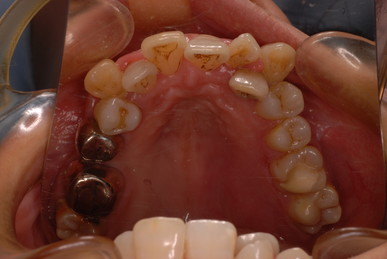

写真左の歯のうち過剰歯と糸きり歯の隣を抜きました。

矯正治療一ヶ月後です。歯並びのガタガタはすぐよくなっています。

歯並びは綺麗になり掃除はしやすくなったはずですが、矯正治療中は

磨きにくいので歯周病や虫歯が酷くなりやすいのです。